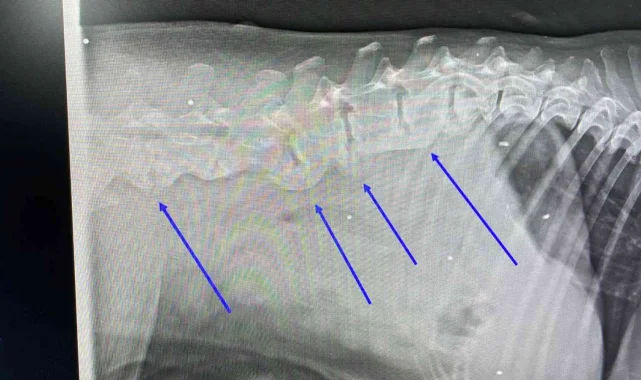

Muğla'nın Bodrum ilçesinde trafik kazası sonucu yaralanan köpeğin çekilen röntgen filminde, daha önce tüfekle vurulduğu ve vücudundaki saçmalarla yaşadığı ortaya çıktı.

Araç çarpması nedeniyle kalçasında kırık olan köpeğin vücudunda onlarca saçmaya rastlandı. Saçmalar, hayvanın daha önce tüfekle vurulduğunu ve vücudunda saçmalarla yaşadığını ortaya çıkardı. Köpeğin ne zaman vurulup ne zamandan beri vücudunda saçmalarla yaşadığı bilinmiyor. Hayvanın tedavisinin özel bir veteriner kliniğinde sürdüğü öğrenildi.